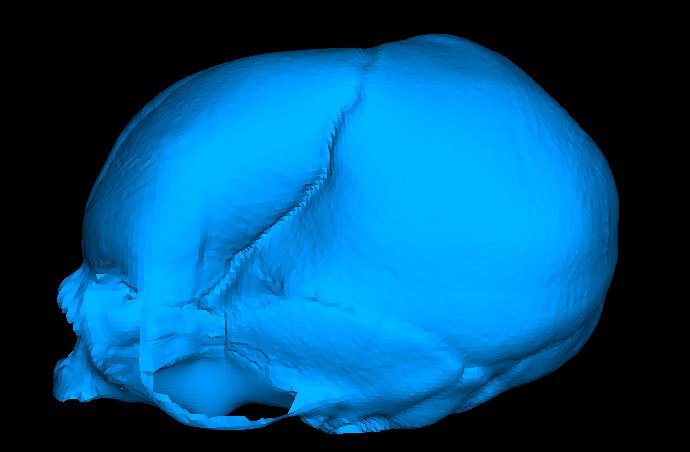

Snapshots of the change of shape of the fetal skull from applying obstetric forceps are shown below (left is undeformed; right is deformed). Note that deformations are magnified with a factor 4.